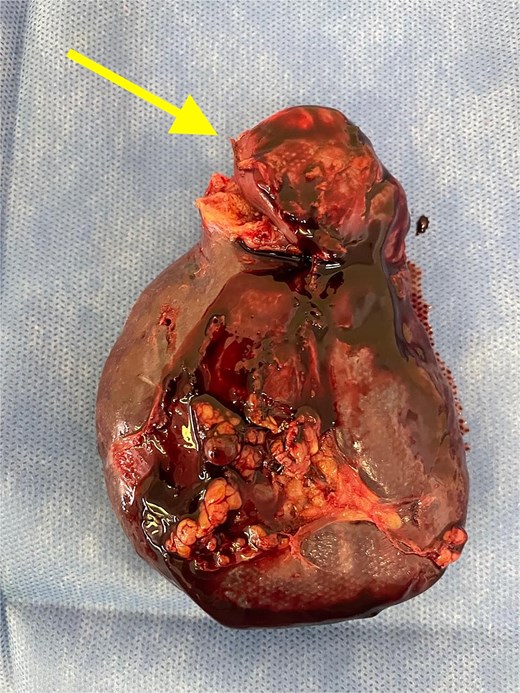

Given the histopathological findings, a laparoscopic splenectomy was performed in a second operative session. The procedure was carried out in the left lateral decubitus position using three trocars. Intraoperatively, a 3 × 3 cm lesion was identified within the splenic parenchyma. The specimen (Fig. 6) was extracted through the previously used Pfannenstiel incision. Histopathological analysis confirmed infiltration by an enteric-type adenocarcinoma (Figs 7–9).

Splenectomy specimen showing the metastatic lesion in the upper pole (arrow).